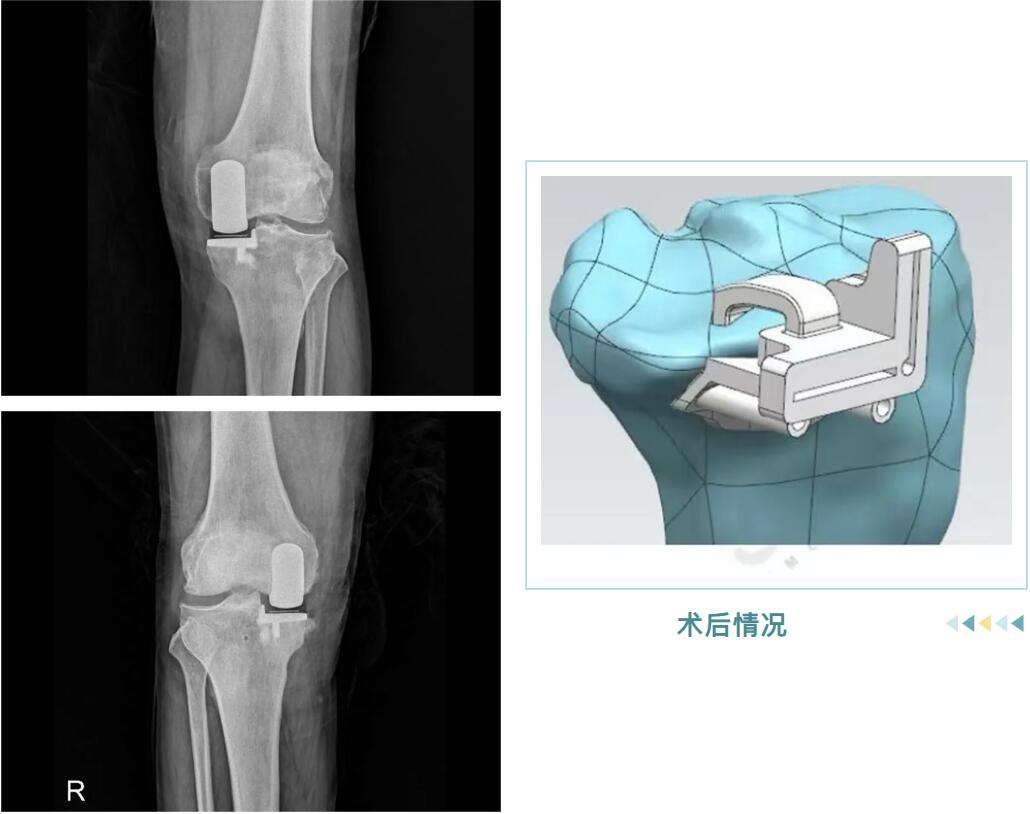

术后情况

从精准的3D术前规划,到罗院长团队娴熟的手术操作,再到术后个性化的康复指导,整个过程高效而顺利。很快,邵阿伯的“罗圈腿”变直了,术后他轻松站起,行走时仿佛时光倒流十年。

它并非换掉整个膝盖,而是用仿生“小垫片”精准替换掉内侧磨损的软骨面。手术仅处理病变部分,保留了您前后交叉韧带和健康的软骨,最大程度维持了膝关节原有的自然运动感和稳定性。